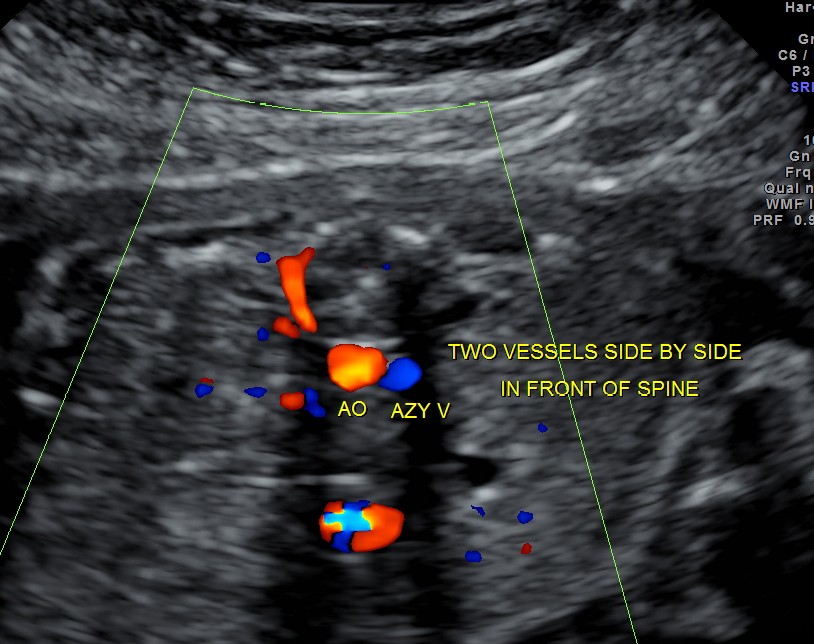

Particular to the diagnosis of Left isomerism or polysplenia syndrome is the demonstration of inferior vena caval interruption with azygos continuation.

double vessel sign seen in front of spine

1. double vessel sign of aorta and azygos vein running side by side , with azygos slightly posterior,